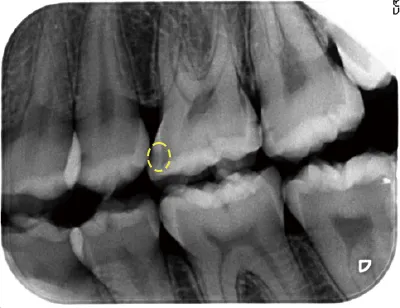

写真1 黄色の破線がむし歯の始まり

写真1の歯はむし歯の始まりを示しています。歯の表面が白く濁っており、エナメル質の結晶が溶け出しているのです。歯に穴があく一歩手前の状態です。